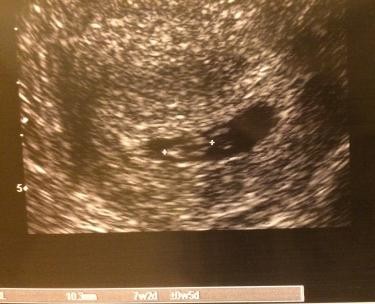

Ultrasound in early pregnancy (before 12 weeks ) - Dating Scan Dating ultrasound A 'dating ultrasound' or 'dating scan' is a scan done early in pregnancy (before 12 weeks ) . It is usually done to check how many weeks pregnant you are and therefore to calculate the estimated due date, but it can be done for other reasons . Only a few women need a dating scan .

The first dating scan is usually done after 10 weeks , and this is the norm all over the world . This doesn't mean that you cant do a dating scan at 8 weeks either . There are many moms who have done the same and have had accurate results .

Due Date Accuracy . Naturally, one of the most common questions asked about ultrasound is : Just how accurate are due dates predicted by ultrasound? Evidence suggests that, in the first 20 weeks of pregnancy, the first ultrasound may be the most accurate tool for calculating a fetus's gestational ages .